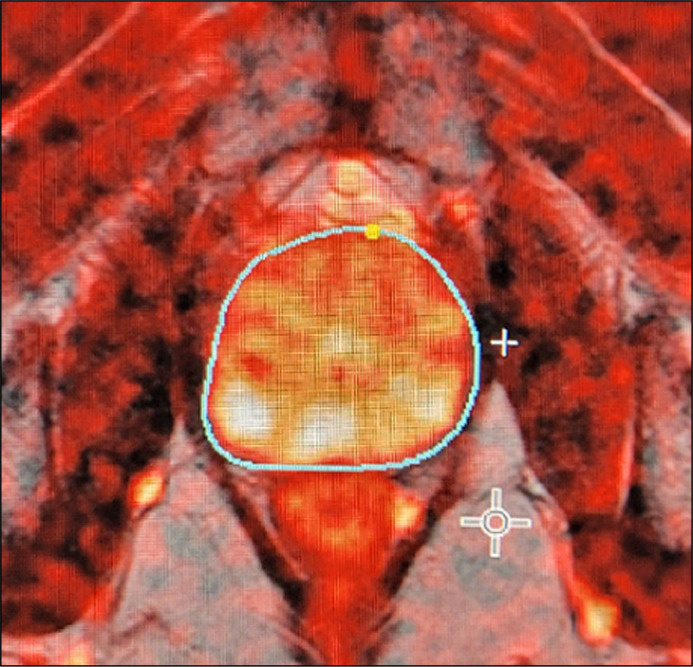

Introduction: The incidence of prostate cancer is increasing in Poland, particularly due to the aging population. This review explores the potential of deep learning algorithms to accelerate prostate contouring during fusion biopsies, a time-consuming but crucial process for the precise diagnosis and appropriate therapeutic decision-making in prostate cancer. Implementing convolutional neural networks (CNNs) can significantly improve segmentation accuracy in multiparametric magnetic resonance imaging (mpMRI).

Results: The results indicate that CNNs, particularly those utilizing the U-Net architecture, are predominantly selected for advanced medical image analysis. All the reviewed algorithms achieved a Dice similarity coefficient (DSC) above 74%, indicating high precision and effectiveness in automatic prostate segmentation. However, there was significant heterogeneity in the methods used to evaluate segmentation outcomes across different studies.